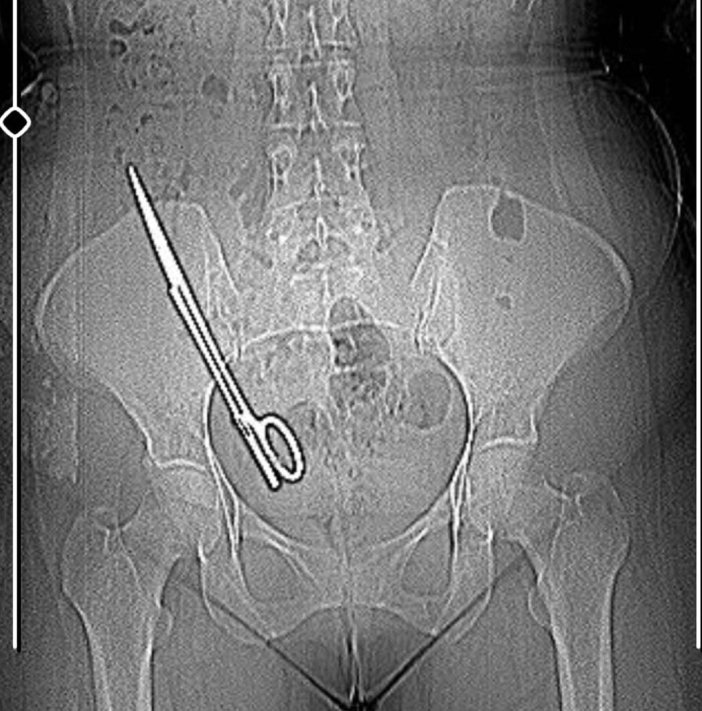

Doktorun tavırlarından şüphelenen Fatma Kala, ameliyat olmayı reddedip KSÜ Sağlık Uygulama ve Araştırma Hastanesi'ne gitti. Burada yapılan tetkiklerde Kala’nın karnında 16 santimetre uzunluğunda makas olduğu tespit edildi. Ameliyatla karnındaki makas çıkarılıp salığına kavuşan Fatma Kala, hastaneden çıktıktan sonra avukatı aracılığıyla 7 yıl önce ameliyatı gerçekleştiren doktor Koray Ş. hakkında Kahramanmaraş Cumhuriyet Başsavcılığı’na suç duyurusunda bulundu.

Karnında makas varken küçük çocuğu ile birçok defa MR odasına girdiğini belirten Kala, “Bundan 7 yıl önce özel bir hastanede ameliyat oldum. O günün gecesinde tekrar iç kanama geçiriyorum ve ikinci ameliyatımı oluyorum. Bu ameliyatta maalesef ameliyat olan bölgemde ameliyat makası unutuyorlar ve biz bunu 7 sonra öğreniyoruz. Baş ağrısından dolayı hastaneye gittik. Hastanede doktorumuz MR'a girmem gerektiğini söyledi. Ben MR teknisyenine daha önce çocukla beraber MR odasına girdiğimde benim sağ tarafımda çekme olduğunu söyledim. Teknisyen bana 'Bu şekilde seni MR'a alamam, çok tehlikeli. Acilen ameliyat olduğun doktoru bul' dedi. Doktorumuz bizi hemen röntgene aldı. Röntgende bir yabancı cisim görmüş ama bize söylemedi, ‘Daha önceki ameliyatından dolayı bir komplikasyon oluşmuş. Seni ameliyat edip dedi o komplikasyonu ortadan kaldırmam gerekiyor’ dedi. Biz doktorun telaşlı tavrından şüphelendik. Eşimle birlikte tıp fakültesine gittik. Oradaki acil doktorlarına başımızdan geçen olayı anlattık. Onlar beni röntgene soktu. Oradan ilaçlı tomografiye girince daha önceki ameliyatımda bırakılan makas orada görüldü. Genel cerrahi bölümünde bu makas çıkarıldı'' diye konuştu.